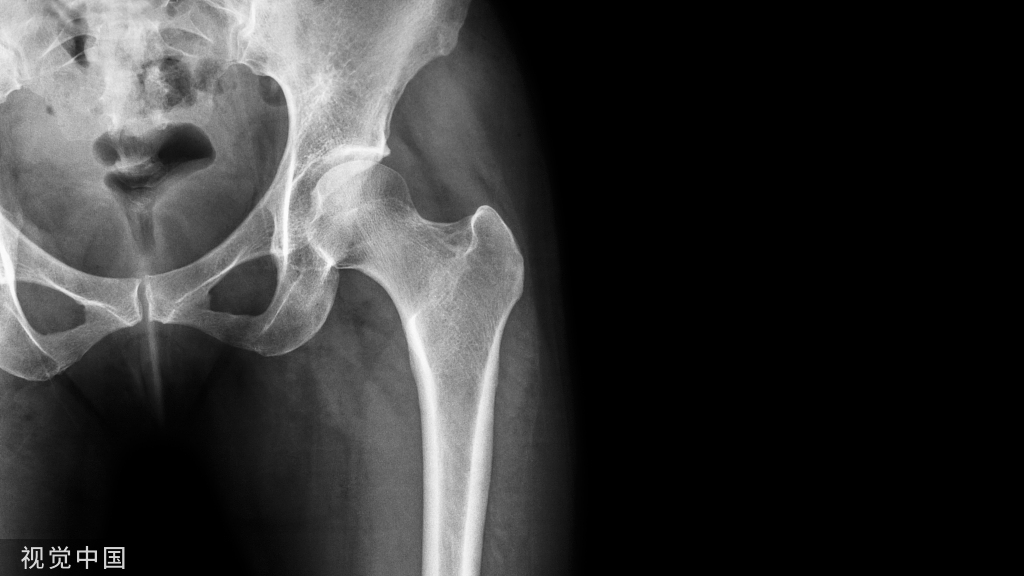

病例:男性,14岁。

CT扫描证实胫骨平台后缘明确骨折。